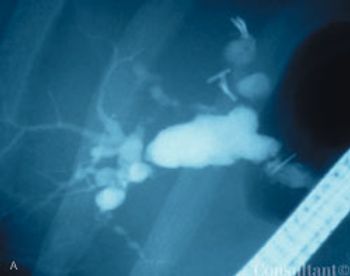

A 41-year-old man complained of upper abdominal pain and malaise of several months duration. He had emigrated to the United States from Korea 5 years earlier.